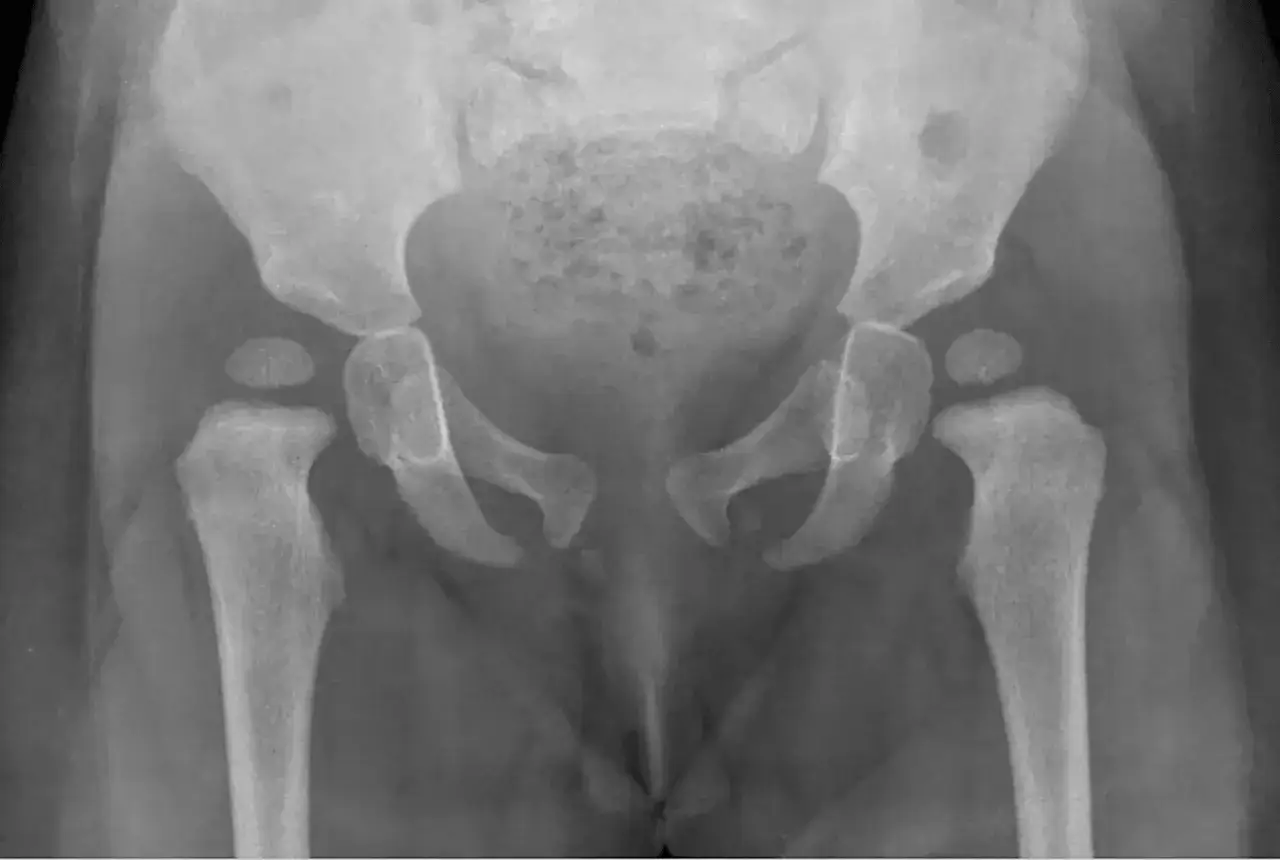

W przypadku podejrzenia dysplazji, lekarz może zlecić badania obrazowe. Najczęściej stosuje się USG stawów biodrowych, które jest bezpieczne i bezbolesne dla niemowlęcia. W niektórych przypadkach może być konieczne wykonanie zdjęcia rentgenowskiego, ale zwykle stosuje się je u starszych dzieci.